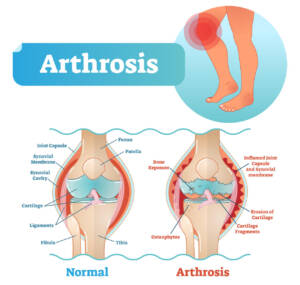

artrosi,

Nell’Ortopedia: ottimi risultati sono stati riscontrati nel reumatismo articolare,

nella gonartrosi, nella protrusione discale e nella coxartrosi.

Trova anche indicazione nel trattamento di malattie a carico di piccole e grandi articolazioni.

Ottima per disturbi muscolo scheletrici come ernia del disco, tunnel carpale,

artrosi del ginocchio

E nelle malattie delle grandi e piccole articolazioni: degenerative, vascolari, infiammatorie e autoimmuni.